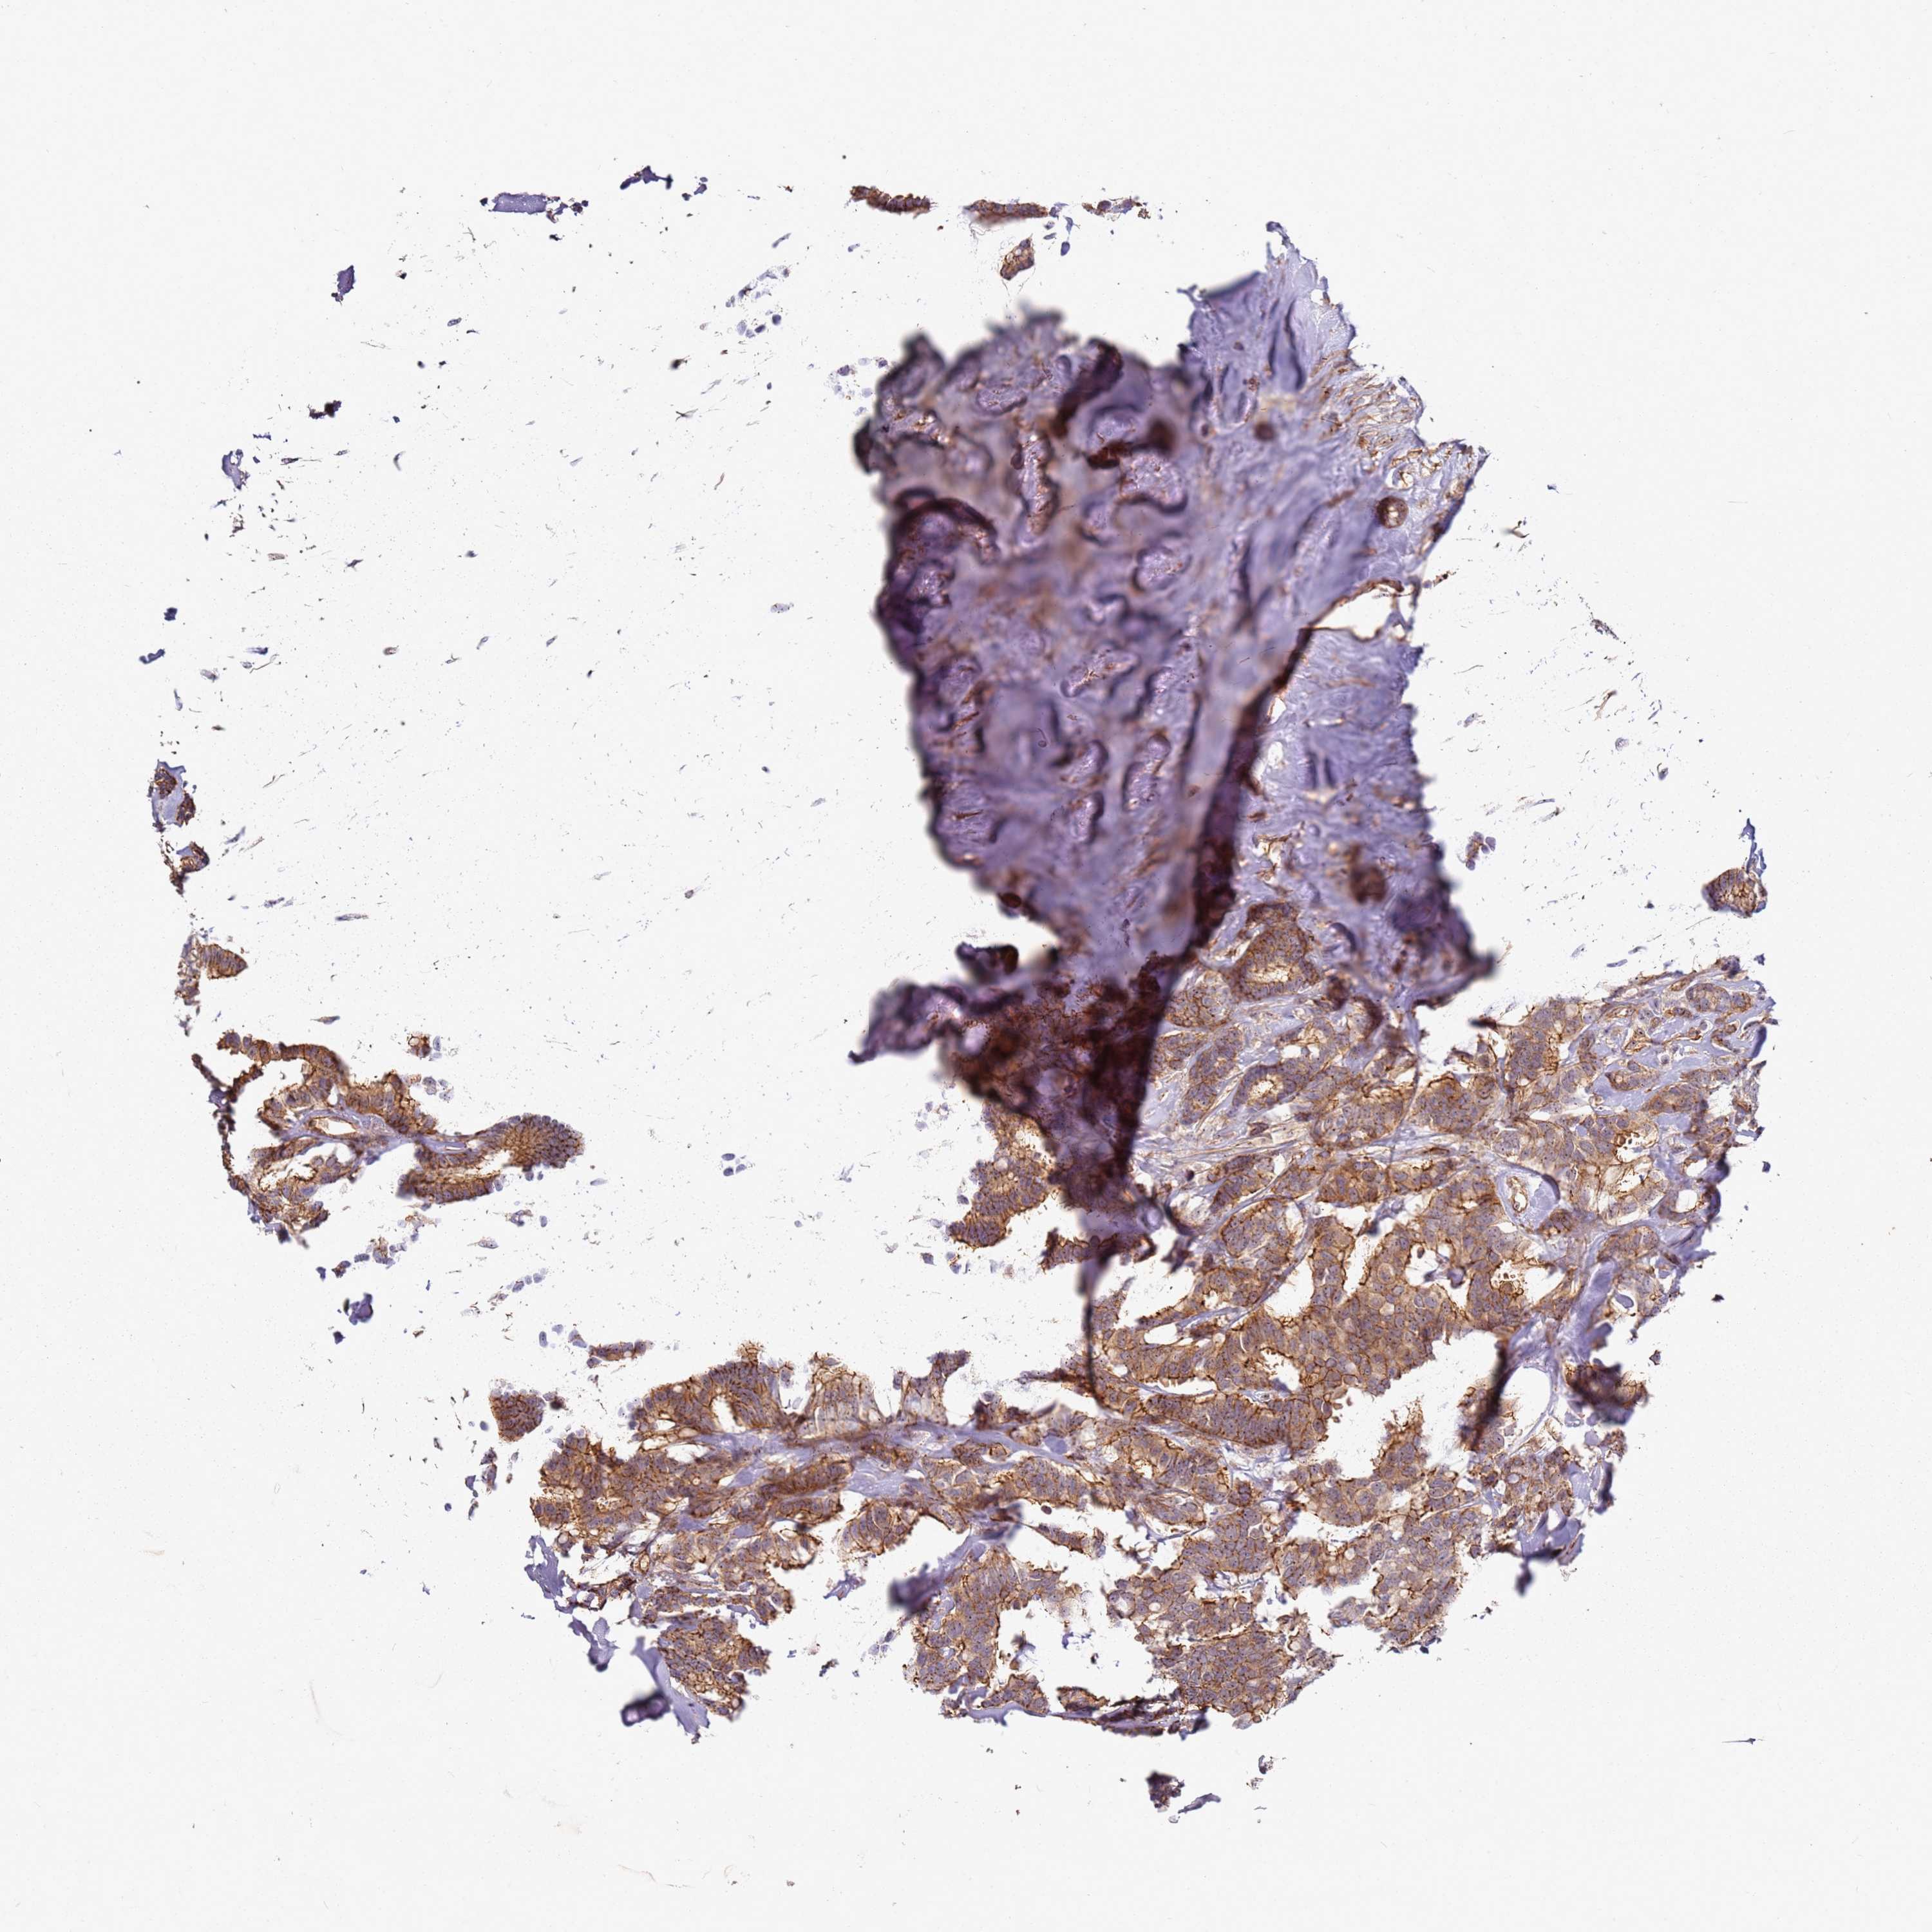

CANCER BREAST CANCER Show tissue menu

BRCA TCGA BRCA VALIDATION PROTEIN EXPRESSION